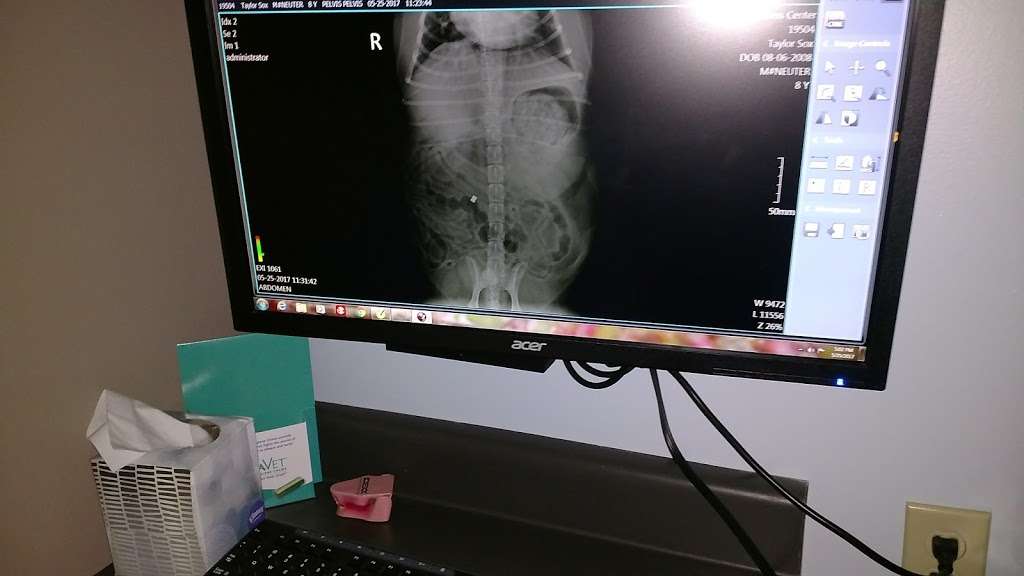

Animal Wellness Center of Pontiac is a full-service veterinary medical and surgical facility located in Pontiac, Illinois. Animal Wellness Center of Pontiac offers many advanced veterinary services and outpatient surgical procedures and radiography and other surgical procedures requiring hospitalization.